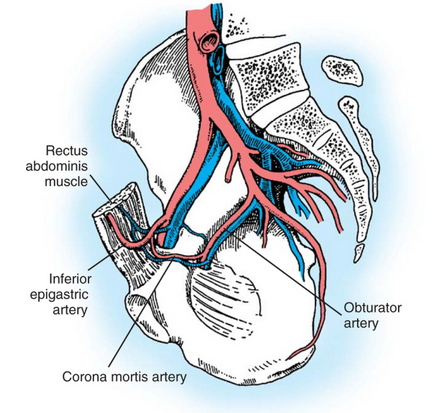

What is the corona mortis and where is it located?

Anastomosis between:

external iliac system or deep inferior epigastric artery

&

obturator system

Lives in the latearl 1/3 of the pubc ramus

Stoppa approach: 4 dangers

Bladder

Corona mortis

External iliac vessels

Obturator nerve & vessels